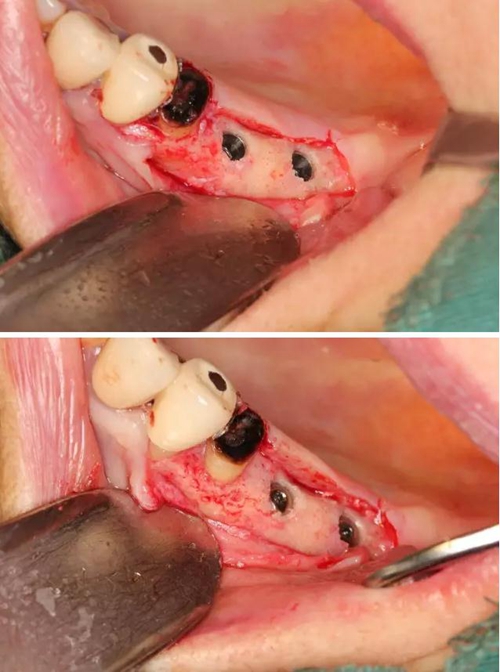

【病例分享】右上內(nèi)提+5冠延長1 梁光強